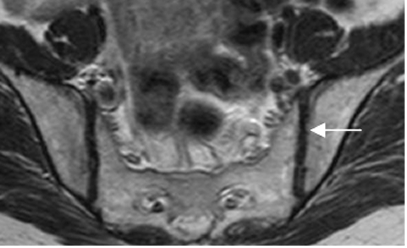

Normalmente se identifica el cartílago articular, como una estructura delgada y con señal de intensidad (SI) intermedia en T1 e hipointensa en T2. (2). (Fig 4 y 5).

Fig 5. Cartílago normal.

RM axial en T2. Cartílago hipointenso.